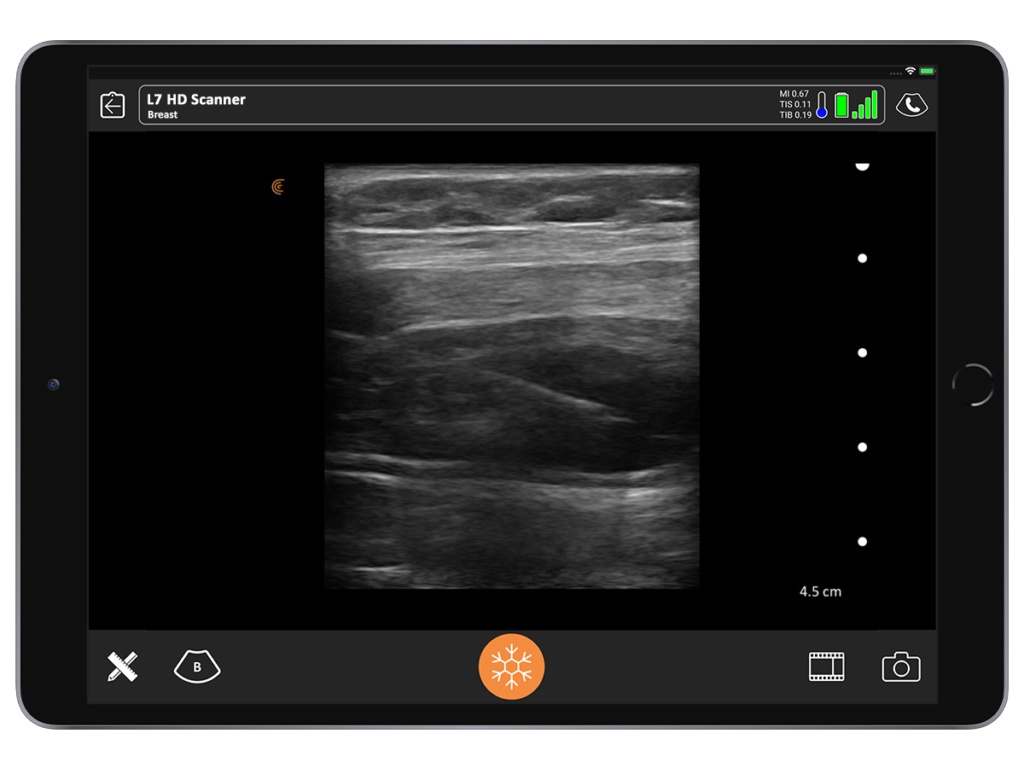

One of the coolest experiences I’ve ever had with ultrasound was being able to clearly see the clinical correlation between what I expected to see and what was actually there. I inherited a patient who had an abdominoplasty 12 to 14 months prior by another surgeon. She had developed a chronic seroma that had been aspirated half a dozen times. A sclerosing agent had been put in to try and stop the fluid buildup. She had both in and out indwelling drains.

When I examined the patient, I noted a huge contour deformity. I knew the plastic surgeon who performed the procedure would not have left this degree of irregularity with liposuction or with the underlying muscle.

When I placed the ultrasound device on the deformity, I could see a black hole that extended all the way up to the area of undermining, from the pubis, around the umbilicus all the way up to the xiphoid. Around that anechoic fluid was thick sclerotic fat. Although I had never seen this, I diagnosed it as a pseudo bursa. I predicted it would look like an orange peel with grungy-looking material on the inside and fluid.

When we saw it in the operating room, it looked exactly as I had seen in the ultrasound. It was the same size. I found it very satisfying.